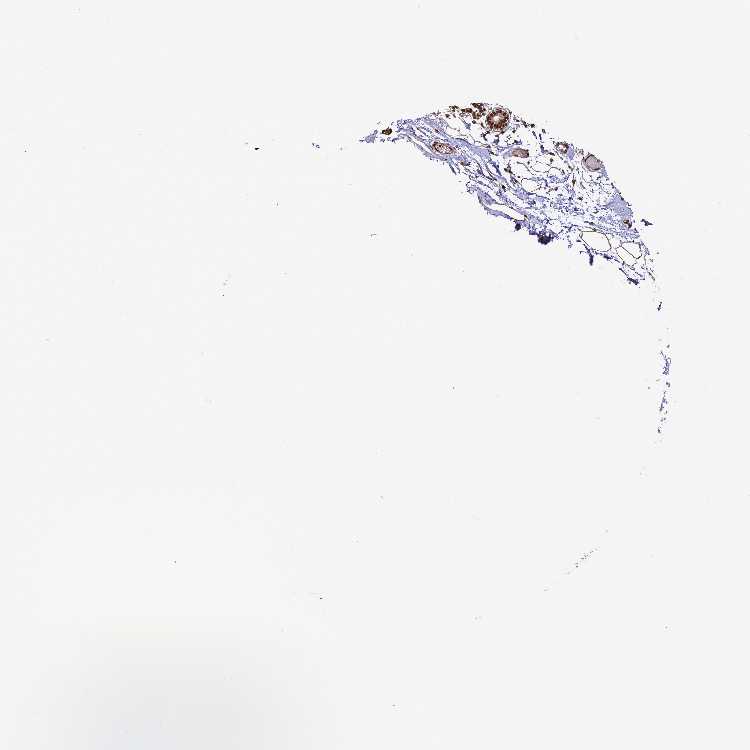

BREAST - Antibody stainingi

Antibody staining in the annotated cell types in the current human tissue is reported as not detected, low, medium, or high, based on conventional immunohistochemistry profiling in selected tissues. This score is based on the combination of the staining intensity and fraction of stained cells.

Each image is clickable and will lead to virtual microscopy that enables deeper exploration of all samples and also displays staining intensity scores, fraction scores and subcellular localization as well as patient and tissue information for each sample.

Antibody HPA001609Antibody HPA001666Antibody CAB010894

Adipocytes Medium--

Glandular cells HighHighHigh

Myoepithelial cells HighHighHigh